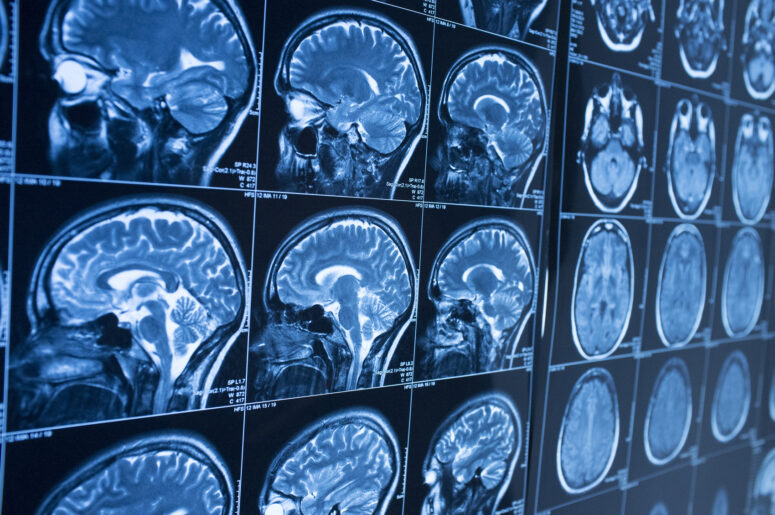

Residents of New York who get into serious accidents risk damage being done to their head, skull and brain. Brain damage in particular can be difficult to deal with because of its long-lasting and highly disruptive impact on a person’s life. Today, we take a look at the recovery process after receiving a traumatic brain injury (TBI).

The Model Systems Knowledge Translation Center (MSKTC) examines the recovery process after a TBI. In severe cases, a person may start out in a state of altered consciousness. This can include being in a coma, a vegetative state, or minimal consciousness. Most of the effects come from the damage done to the soft tissue of the brain. Therefore, symptoms will decrease as swelling, bruising and bleeding within the brain does.